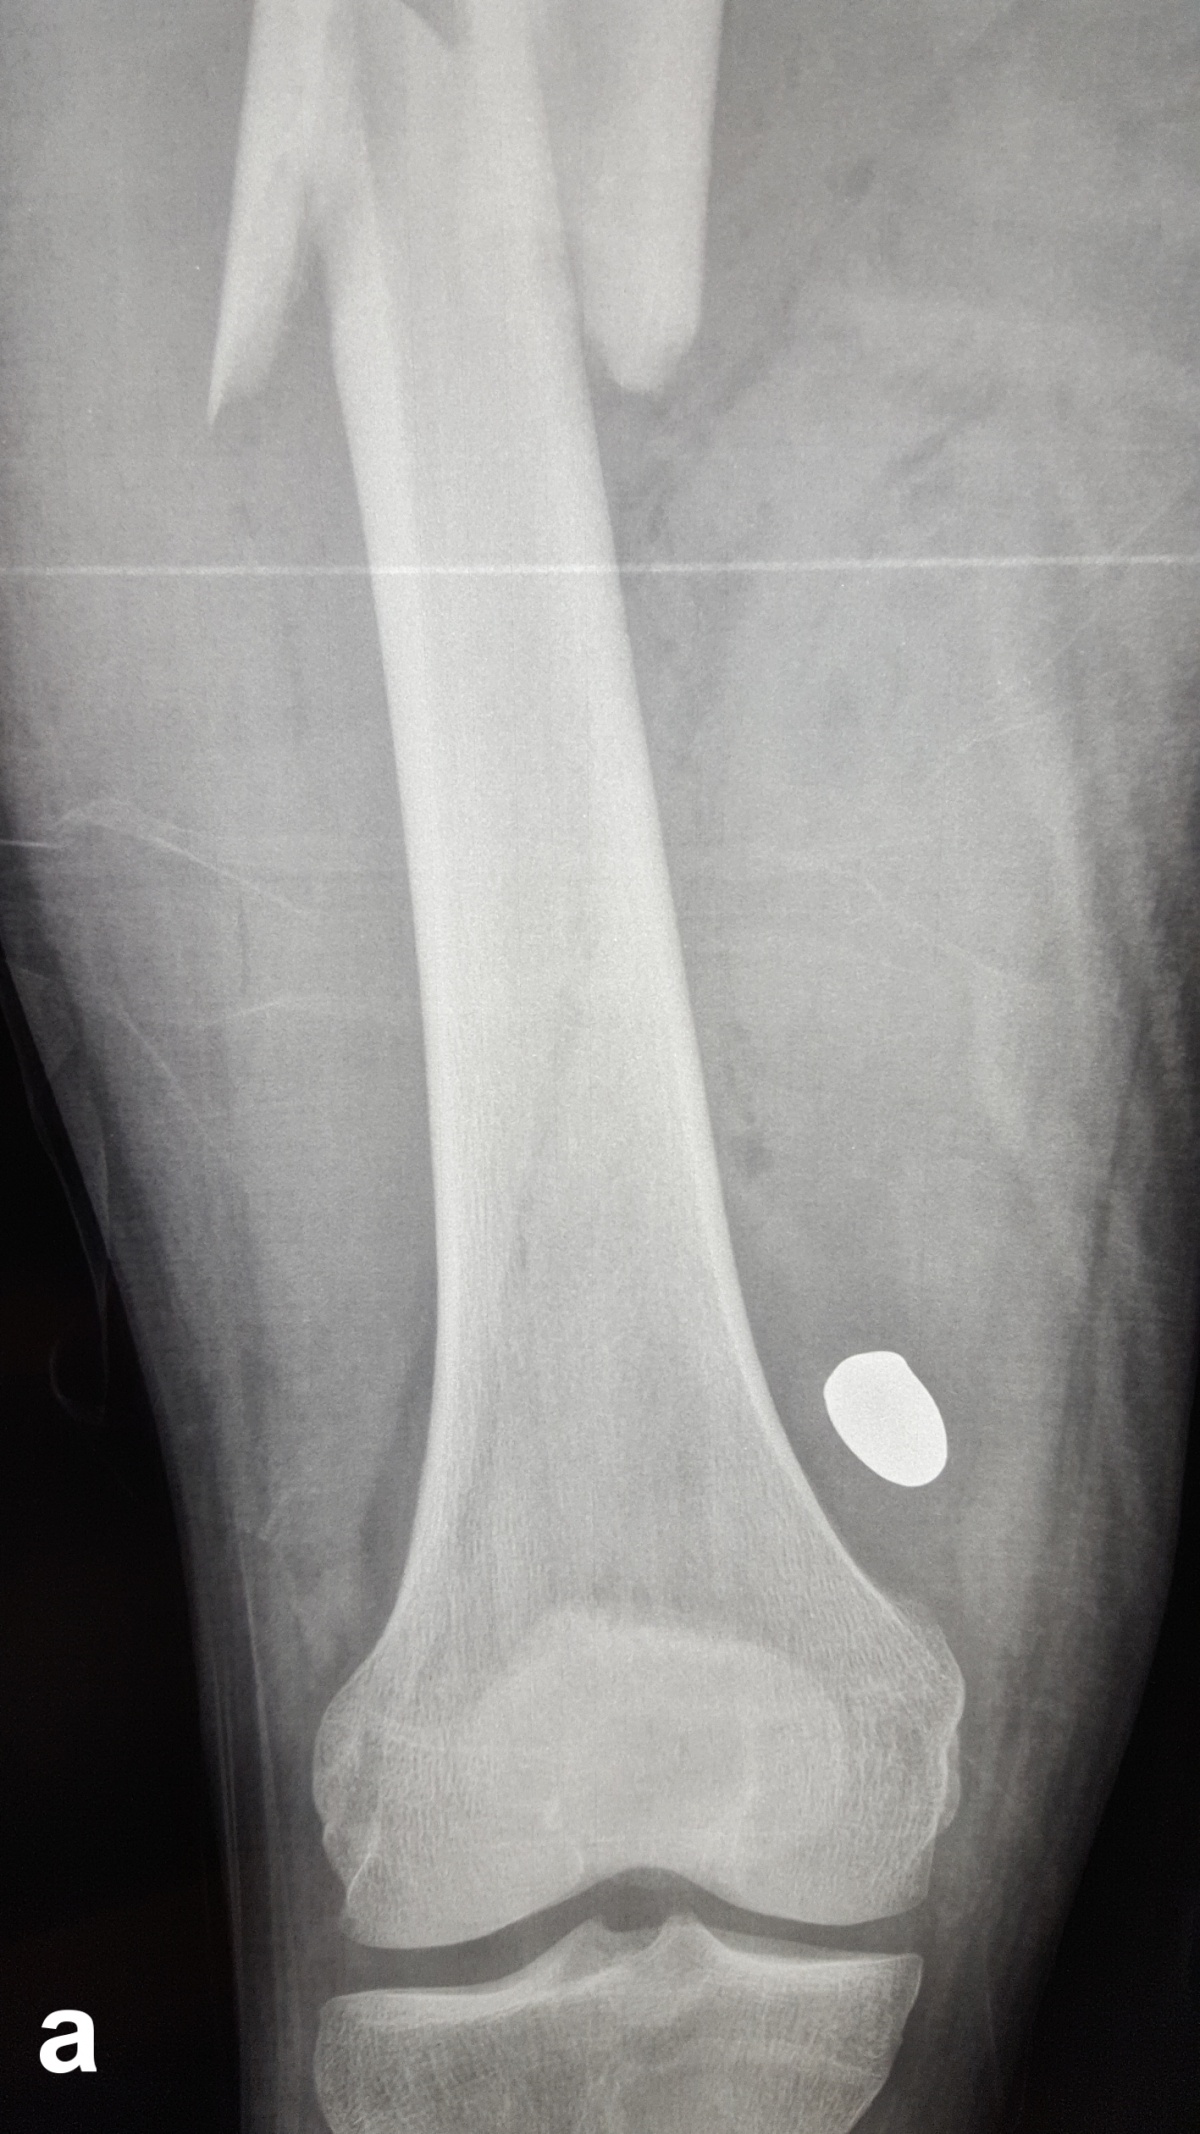

Es zeigt sich das typische Bild einer Schussfraktur nach Niedrigenergieverletzung. a seitlicher Strahlengang,

b a. p. Strahlengang

Beim Auftreffen des Projektils im Rahmen von Niedrigenergieverletzungen auf Knochengewebe entsteht meist eine typische, einfache Fraktur (Abbildung 2). Hochenergieverletzungen des Knochens münden in eine multifragmentäre Situation, bei der ein Großteil der Projektilenergie an den Knochen abgegeben wird. Insbesondere lange Röhrenknochen können, da sie wie eine starre, spröde flüssigkeitsgefüllte Röhre agieren, durch Projektile mit hoher Energie explosionsartig zerstört werden (Abbildung. 3).